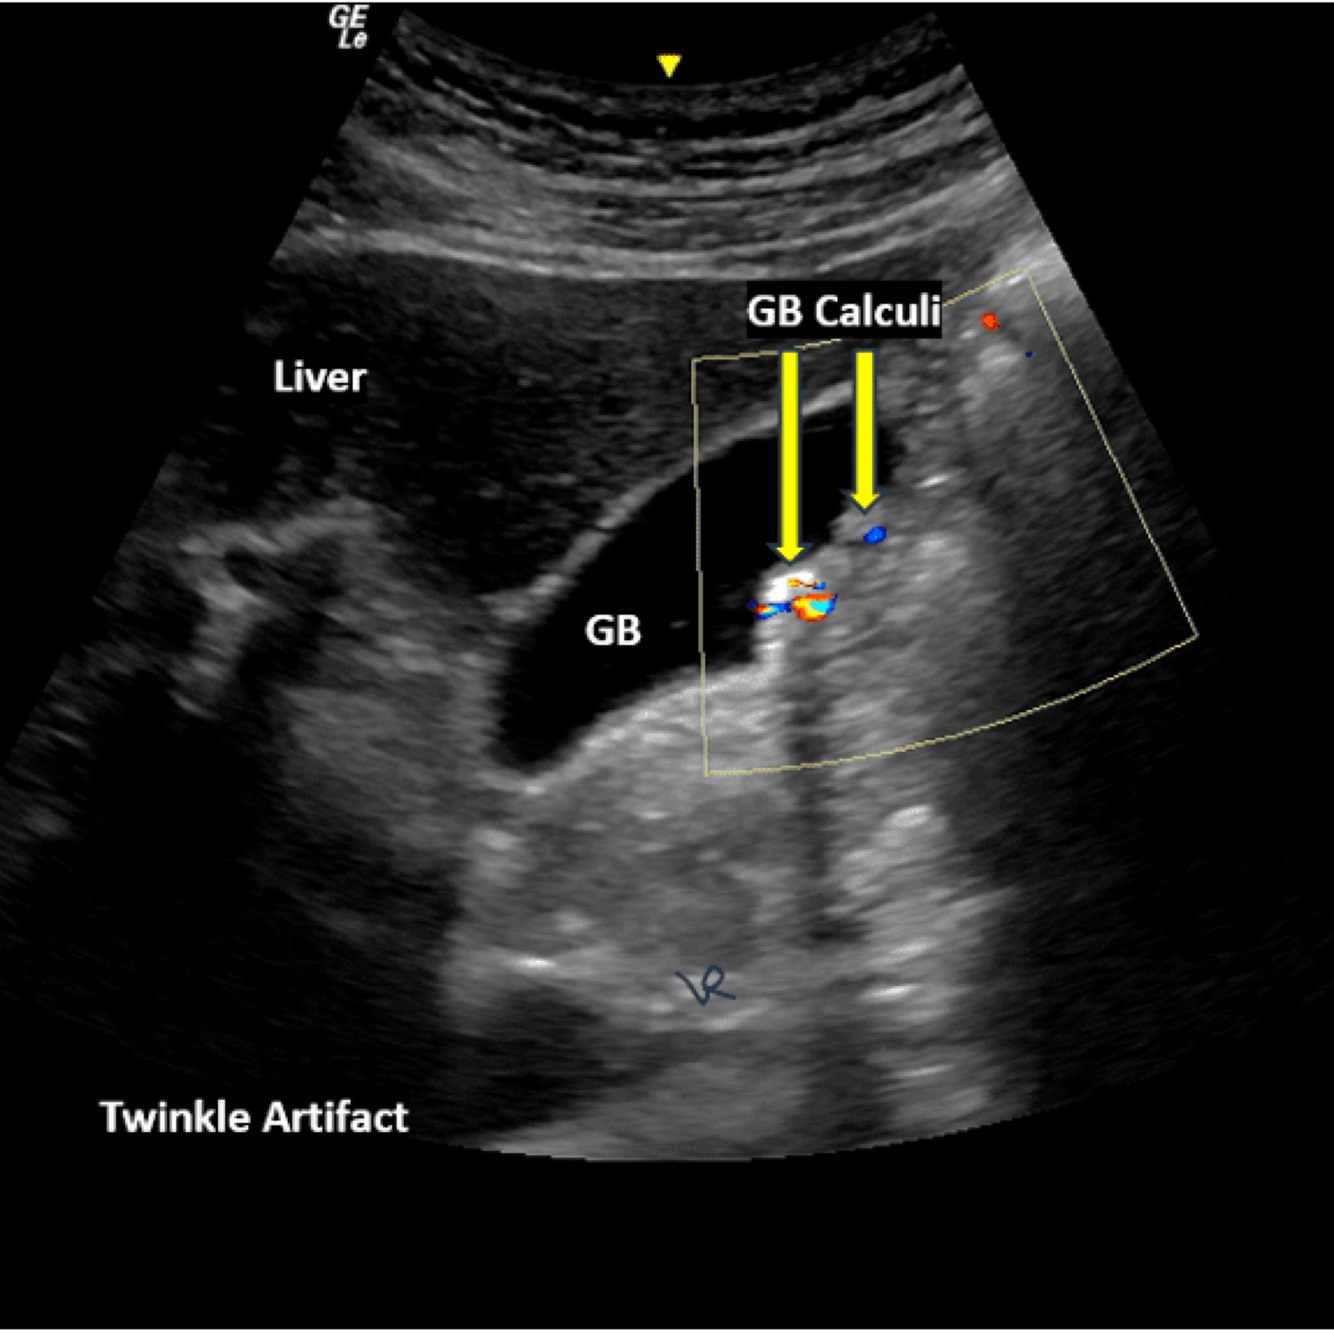

A

Cholelithiasis